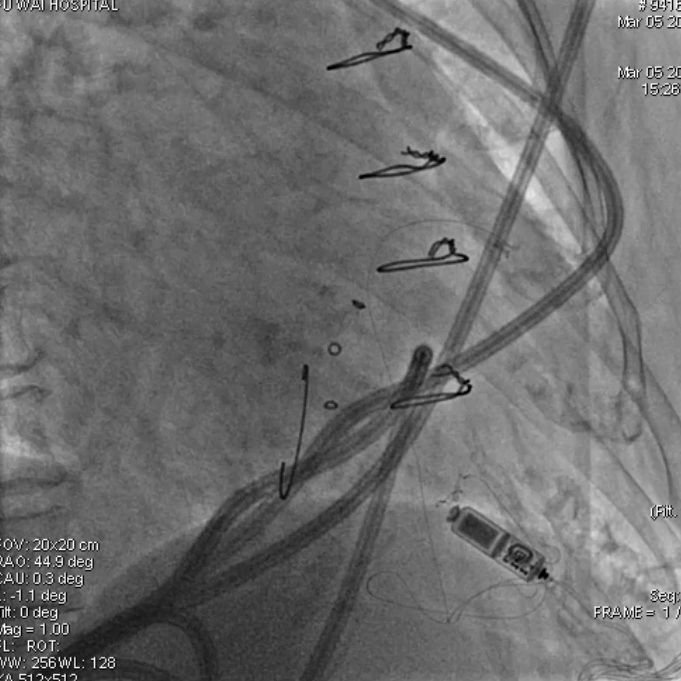

2015年,中国医学科学院阜外医院参与了Micra全球上市前临床试验,总共入组了5名患者。该临床试验为全球多中心、非随机、单臂上市前临床研究,旨在评估Micra VR无导线起搏器的安全性和有效性。该项研究的结果发表在2015年新英格兰医学杂志上,研究结果表明,Micra VR无导线起搏器手术成功率为99.2%,其不良事件发生率相对于传统起搏器降低了48%。

近期,中国医学科学院阜外医院将10年前入组的5名无导线患者在十年内的随访数据加以整理汇总,汇编了国内首批应用无导线疗法的长期的、真实世界临床结果。

5名患者中, 2名患者因恶性肿瘤及肺部感染分别于2019年和2022年离世。3名患者随访已达到10年,相关数据整理如下